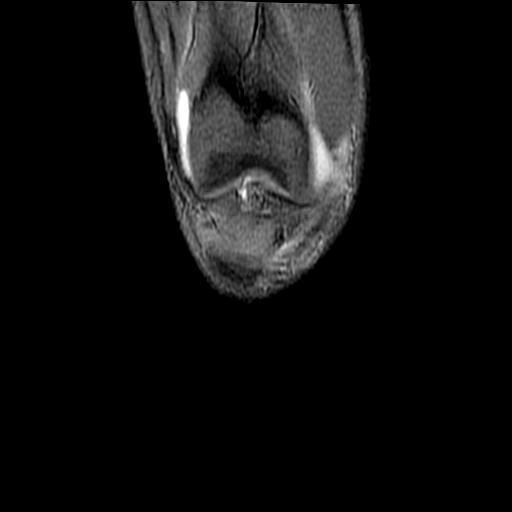

40岁男性,右膝关节外伤,x光平片示,髁间隆突撕脱骨折。

1、前交叉韧带撕裂;

2、外侧半月板后角撕裂;

3、关节腔积液。

髁间隆突撕脱骨折;内侧副韧带损伤。

1、内侧副韧带撕裂;

2、前交叉韧带撕裂;

3、滑膜炎伴关节腔积液。

1、前交叉韧、内侧副韧带撕裂;

3、关节腔积液。4、髁间脊撕脱骨折。